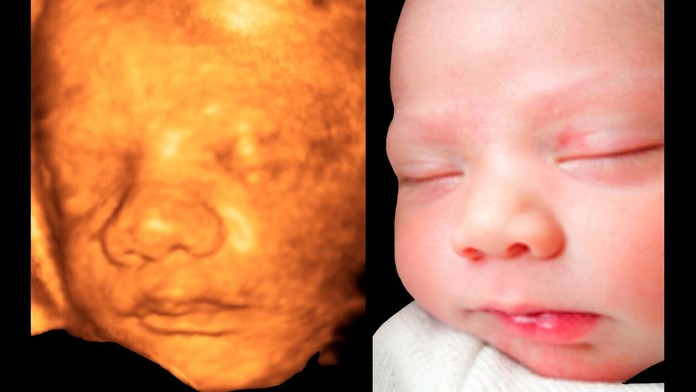

Nové šokujúce fakty. Alkohol počas tehotenstva mení bábätku črty tváre

ilustračná snímka

Zdroj: Profimedia.sk

Aj malé množstvo alkoholu vypitého počas tehotenstva môže zmeniť črty tváre bábätka. Vedci skúmali fotografie tvárí 415 ročných detí a zaznamenali zmeny väčšinou okolo nosa, očí a pier. Zmeny sú spojené so všetkými úrovňami konzumácie alkoholu. Je jedno, či si matka vypila v prvom trimestri alebo v neskoršom štádiu tehotenstva. Píše Independent.co.uk.

Ide však o také jemné zmeny v črtách tváre, že neboli viditeľné voľným okom. Výskumníci použili sofistikovaný 3D zobrazovací softvér, ktorý rozdelil tvár dieťaťa na takmer 70-tisíc dielov. Porovnali tváre detí matiek, ktoré počas tehotenstva nepili vôbec a tými, ktoré pili alkohol aj v čase, kedy boli v očakávaní.

So zmenami tváre dokonca spojili aj nízke hladiny alkoholu - napríklad príležitostné dva poháre drinku. To však nevyhnutne neznamená, že pitie malého množstva alkoholu škodí plodu. "Nevieme, či sú malé zmeny v črtách tváre detí akokoľvek spojené s rozdielmi vo vývoji," povedala vedúca výskumu Jane Halliday z Destkého výskumného ústavu Murdoch v austrálskej Victorii. "Plánujeme však sledovať aj to, ako deti rastú," dodala.

V zmenách čŕt tvárí zaznamenali napríklad, že deti mali o niečo kratší alebo vytŕčajúci nos. Táto charakteristika tváre je spojená s fetálnym alkoholovým syndrómom. Ide o dôsledok ťažkého pitia počas tehotenstva. S týmto stavom sú u detí spojené aj menšie oči, tenké horné pery, poruchy pozornosti a správania sa.

Zo všetkých 1 570 žien, ktoré sa zapojili do austrálskeho prieskumu, až 27 percent uviedlo, že počas tehotenstva pili alkohol.